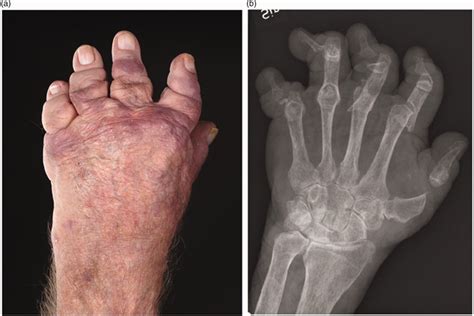

Cualquier forma de psoriasis puede acompañar a la artritis. La AP es una enfermedad inflamatoria articular y extraarticular. La mayoría de pacientes presenta mono, oligo o poliartritis de grandes o pequeñas articulaciones. Normalmente es una enfermedad asimétrica, a diferencia de la AR, y se distingue por la afectación de las articulaciones IFD. Menos del 5% de los pacientes presentan una forma grave, la artritis mutilante (fig. 1).

Figura 1 Artritis mutilante.